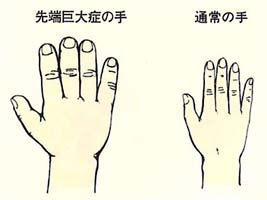

2割強の腺腫が成長ホルモンを分泌します。思春期に発症した場合は、身長や手足が異常に伸びいわゆる巨人症となります。

一方、成長してから発症した場合は、先端巨大症となります。これは手足の先端、額、あご、くちびる、舌等が肥大することで指輪やクツのサイズが合わなくなってきます。そのため顔つきは数年間でかなりかわってしまいます。成長ホルモンが長期間異常値を示していると、糖尿病、心不全、動脈硬化症や直腸癌等を合併し寿命が短くなります。